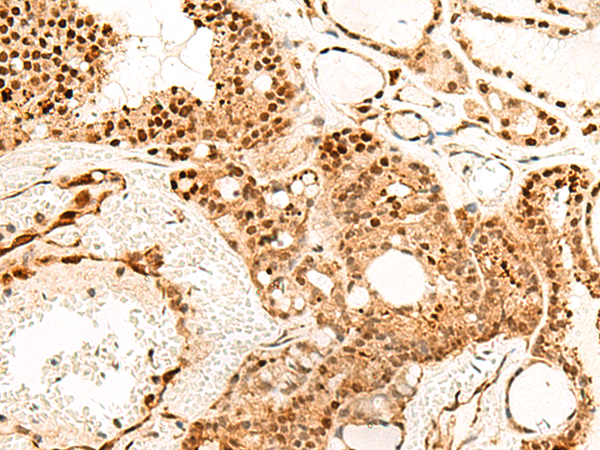

分类: 科研抗体货号: P00545别名: MPF; SMRP应用: IHC反应种属: Human